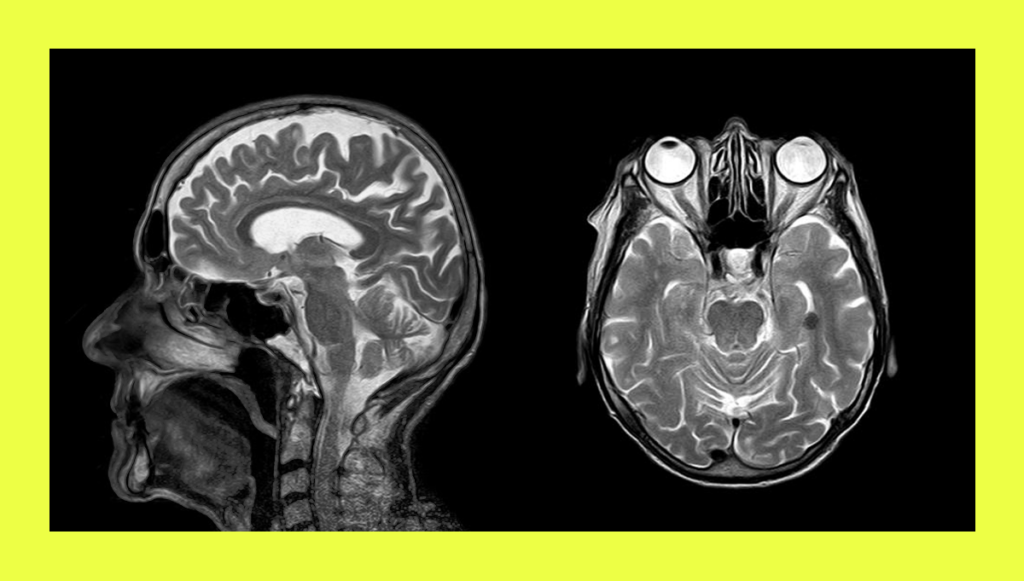

В 2019 году Алик получил травму головы. В больнице ему диагностировали отёк мозга и через некоторое время провели трепанацию черепа (в распоряжении редакции есть выписной эпикриз).

Из-за травмы у него отнялась левая рука, а после операции стали происходить эпилептические приступы — они случаются и по сей день, говорит Мира. Также в больнице у Алика были истерики, он агрессивно себя вёл и с трудом подпускал к себе врачей.

В ноябре этого года Алику предстояла операция по установке металлической пластины в череп. Но состоится ли она теперь — неизвестно. 24 сентября Алик получил повестку от военкомата.

Как объяснили «Вёрстке» юристы, специализирующиеся на призывном праве, в военкоматах медики должны проводить медосвидетельствование мобилизованных и по итогу принимать решение о проведении военно-врачебной комиссии в госпитале. Эта комиссия должна вынести заключение об изменении категории годности до «Д» — не годен к несению службы. Впоследствии это заключение передаётся на утверждение в вышестоящую окружную военно-врачебную комиссию. Если она подтверждает выводы медиков, военнослужащего должны уволить.

Когда Алик проходил медкомиссию в военкомате, ему действительно предложили понизить категорию годности, но всего лишь с «А» до «Б–3»: такая категория присваивается при незначительных нарушениях функций каких-либо органов и позволяет нести службу.

Несмотря на эпилепсию и на то, что Алик не может двигать левой рукой, врачи в пензенском военкомате «не нашли» оснований для проведения военно-врачебной комиссии в больнице. Кроме того, по словам Миры, они ввели Алика в заблуждение, сказав, что проводить комиссию якобы уже поздно и нужно было делать это до отправки на сборы.